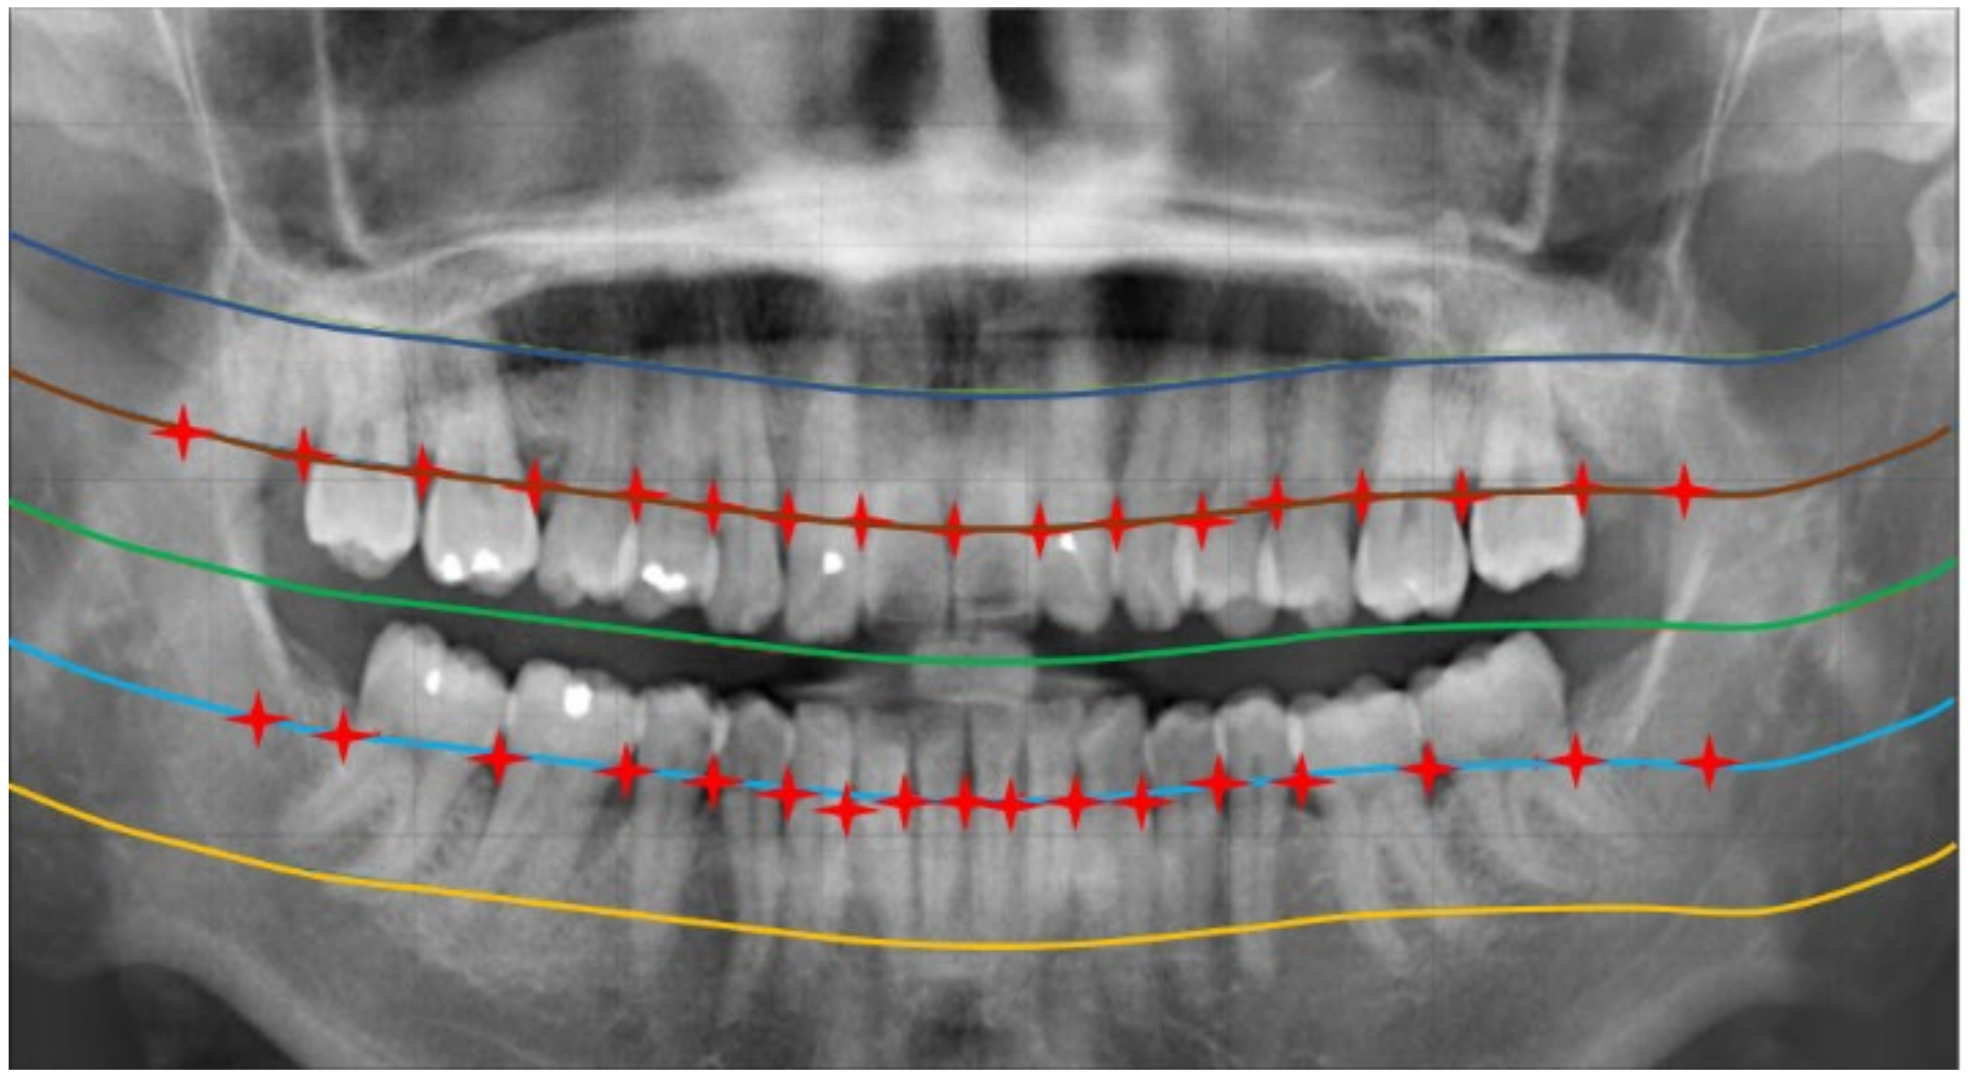

2.2.1. Curve of the Mouth

2.2.2. Curve Adjustment

2.2.3. Positioning Numbers